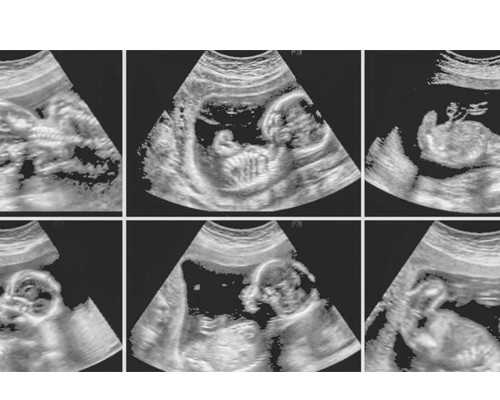

今年突然3个月不来月经,去打B超,发现子宫内膜厚约19mm,当场吓哭!从小月经量就不小,也不记月经日子,应该一直就不规律,少则推后一周,多则偶尔一两个月。医生说我这种情况可能需要刮宫检查,但是我感觉很害怕。请问内膜厚一定要进行刮宫手术吗?